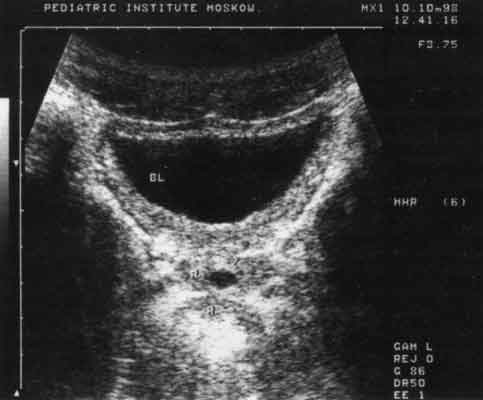

Хронические запоры у девочек являются причиной развития цистита и/или пиелонефрита, причем добиться положительного эффекта при лечении этих заболеваний бывает крайне затруднительно. Ликвидация же хронического запора сразу ведет к нормализации состояния мочевыводящих путей (рис. 9).

Рис. 9. Эхограмма мочевого пузыря при цистите (поперечный срез). Имеется резкое утолщение его стенок.